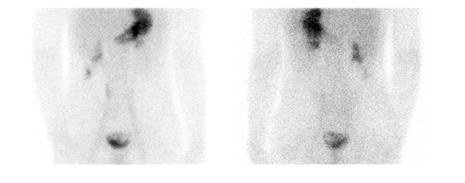

Figure 2 : Étude aux globules rouges avec marquage in vitro (UltratagTM) chez adolescente avec saignement occulte entrainant une anémie sévère. Acquisition dynamique ( A ) et rendu 3D de l’acquisition tomographique (B). Scintigraphie de Meckel sans interférence effectuée 12 jours plus tard. Acquisition dynamique ( C ) et rendu 3D de l’acquisition tomographique ( D ). Les deux études se sont avérées négatives et malgré une investigation extensive, la source du saignement n’a pas été identifié.

Figure 4 : Patient de 13 ans. Rectorragies avec chute de l’hémoglobine. Administration de Zantac IV deux heures avant la scintigraphie. Mise en évidence d’élution au niveau du duodénum et du grêle mais également d’un diverticule de Meckel au flanc droit, près du rein, mieux identifié sur l’étude tomographique. Étude dynamique ( A ) et statique (B) en incidence antérieure, rendu 3D du SPECT (C) et image de fusion (D).